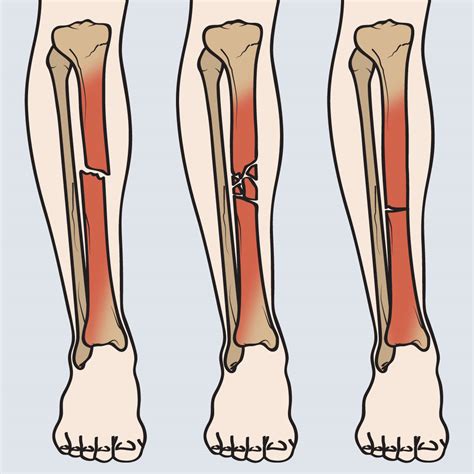

Classification of Tib Fib Fractures

Tib Fib Fractures are classified based on the location, pattern, and severity of the break. Common classifications include:

Classification Description

Proximal Tib Fib Fracture Occurs near the knee joint.

Midshaft Tib Fib Fracture Occurs in the middle of the tibia and fibula.

Distal Tib Fib Fracture Occurs near the ankle joint.

Open Tib Fib Fracture The bone breaks through the skin, increasing the risk of infection.

Closed Tib Fib Fracture The bone does not break through the skin.